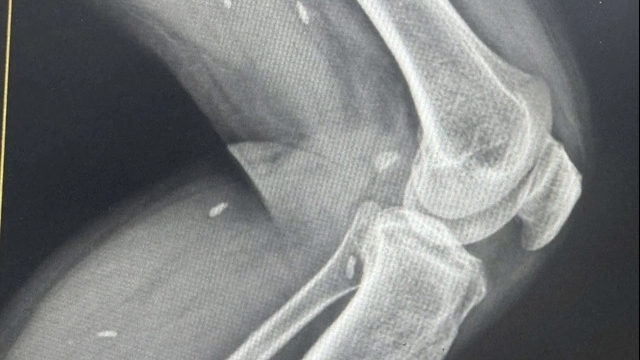

Bài viết đăng trên Tạp chí The Lancet cho biết tim bệnh nhân ngừng đập sau khi bị tổn thương phế nang. Đây những túi nhỏ như quả nho trong phổi giúp đưa oxy vào máu và loại bỏ carbon dioxide. Các xét nghiệm máu của bệnh nhân đã tử vong vì Covid-19 cho thấy “nồng độ” cao một loại tế bào chống nhiễm trùng trong các phần phổi bị tổn thương nghiêm trọng.

| Hình chụp tổn thương phổi bệnh nhân qua đời vì Covid-19. Ảnh: The Lancet. |

Nghiên cứu trường hợp của bệnh nhân Trung Quốc đã cung cấp góc nhìn sâu sắc hơn về tác hại của virus corona với người nhiễm. Các phân tích như trên thực hiện khá khó khăn bởi dữ liệu của tử thi hoặc sinh thiết hầu như không có sẵn hoặc không được phép thâm nhập.

Hình ảnh X-quang của bệnh nhân cho thấy phổi bị tổn thương nhanh và có một số điểm khác biệt giữa hai bên phổi. Ngoài ra, các thay đổi mô học trong tim khiến các nhà nghiên cứu đặt giả thuyết bộ phận này bị virus corona tàn phá.